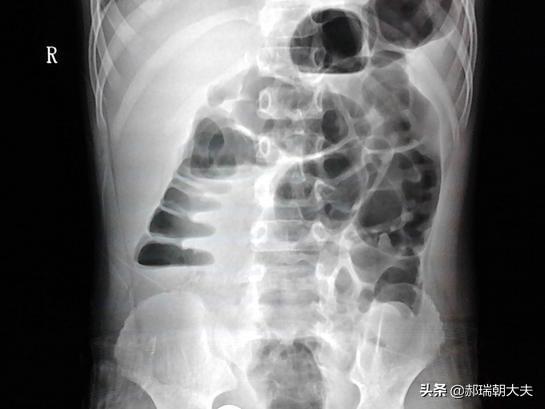

もちろん、通常はこのようなことは起こらないが、腸閉塞の場合に限っては、さまざまな理由で腸が閉塞し、閉塞部の近位にある内容物を下方に排出することができない。

腸閉塞の典型的な症状は、疼痛、嘔吐、膨満感、閉鎖感である。疼痛:腹痛、膨満感:腹部膨満感、閉鎖感:ガスが排出されず便意がない、嘔吐:一晩中食べた内容物を伴う嘔吐で、腸閉塞の程度が低い場合は便臭、腸閉塞の程度が高い場合は酸性臭を伴う。